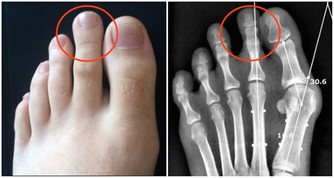

食指下的第二掌骨直接對應全身,從最靠近指尖的位置算起,分別對到:頭、頸、上肢、肺心、肝、胃、十二指腸、腎、腰、下腹、腿足,堪稱是人體縮小版。